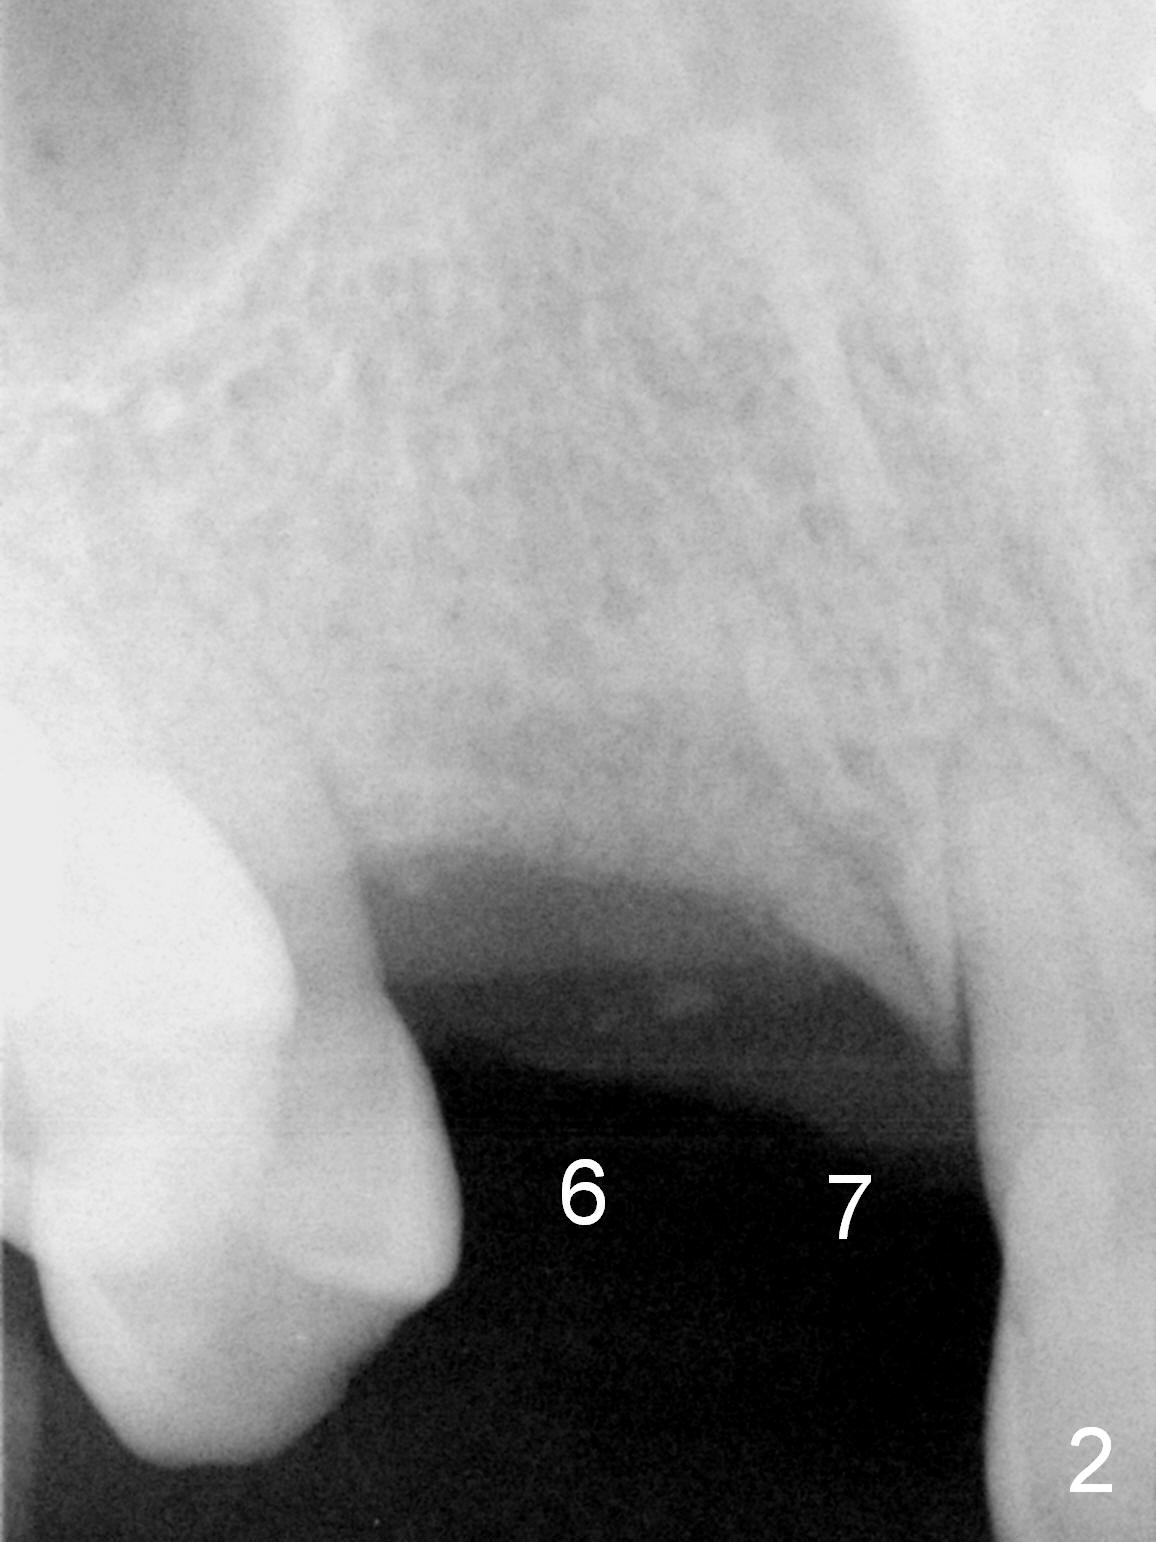

A 54-year-old man has crowded dentition with moderate to advanced periodontitis (Fig.1) and bruxism (exostosis (Fig.6 *)). It is essential to re-establish complete dentition by placing implants at #6, 7 and 15 initially and more when other teeth are lost. The ridge at #6 and 7 is moderately atrophic (Fig.7), while that at #15 severely atrophic (Fig.8). Due to narrow mesiodistal space at #6 and 7 (Fig.2), narrow and 1-piece implants may have to be placed (Fig.3).